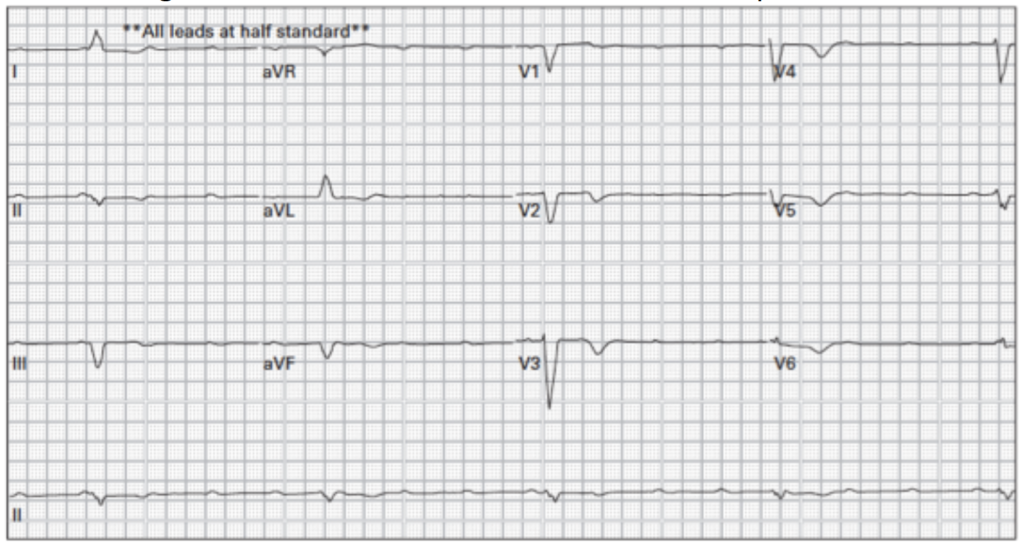

Masculino de 56 años con dolor torácico. ¿Cuál es la arteria probablemente comprometida en este paciente?